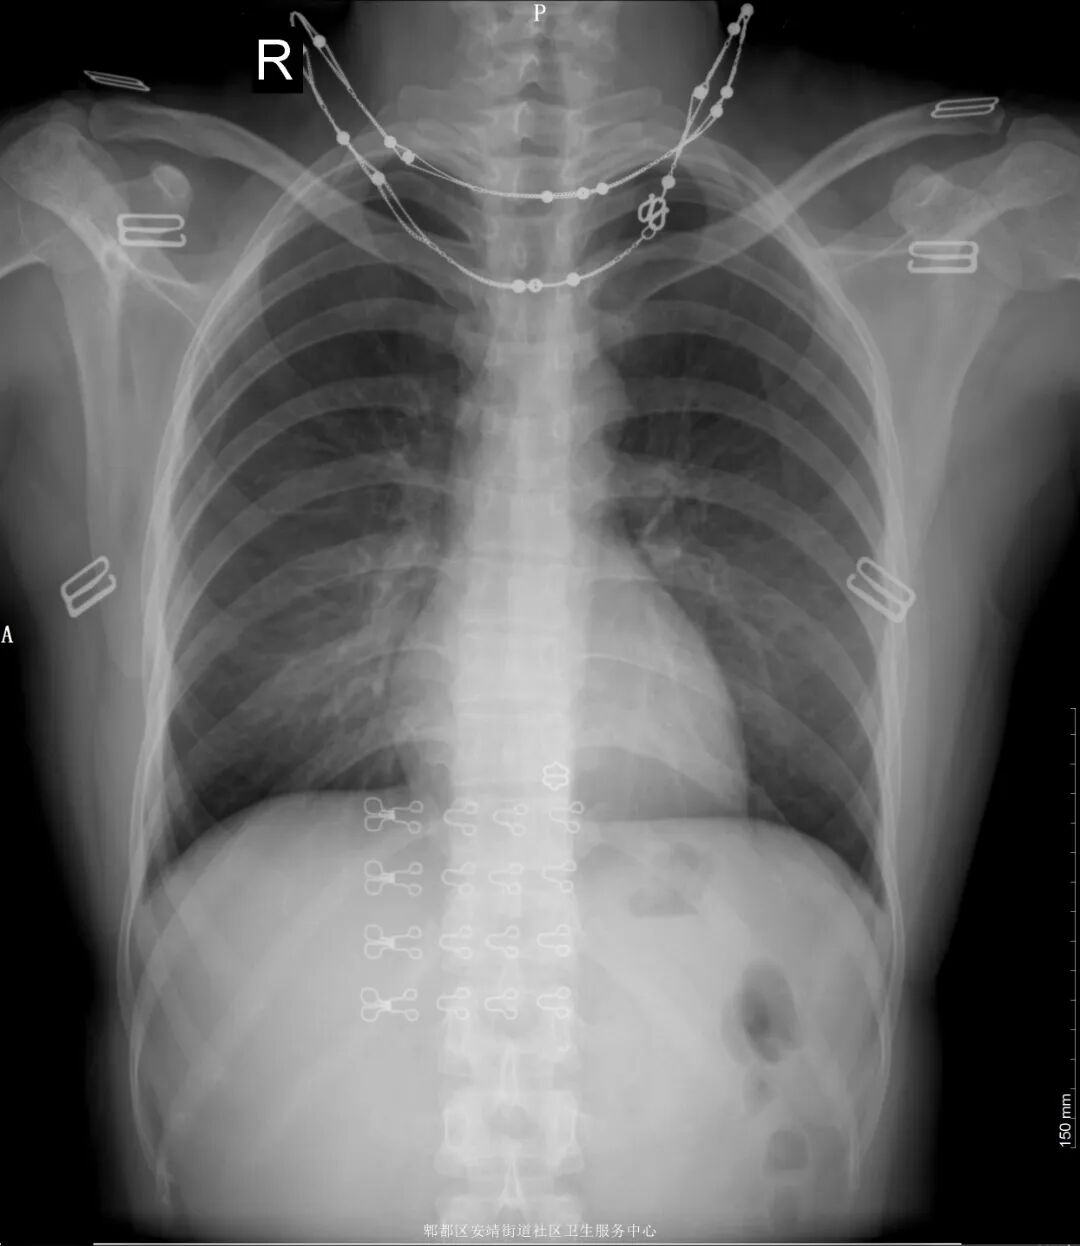

我在再来看看图2,这是没有脱掉内衣拍的胸片。对比第一张,我们可以清楚看到戴在脖子上的项链和内衣的扣子、钢圈。这些体外的异物跟我们要观察的骨头、肺部重叠了,如果刚好这些部位有病灶,这些体外的异物就会形成遮挡,容易导致漏诊及误诊。